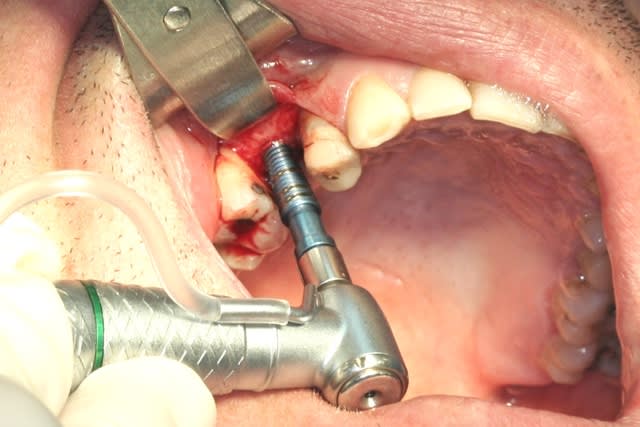

tiens...un ptit cas...

dans ce petit cas...j'ai commencé avec le kit MIS...et fini ma voie crestale avec le kit HBS...

ok, c'est un mini soulevé...mais bon , c'est un exemple...

juste une précision...premier foret 1.3mm sur 8mm...expansion pour mettre un implant de 4x10...

j'ai juste "léché" la préparation du site final avec le foret terminal du système...sur 8mm...avant d'insérer l'implant...stab primaire au top...blocage à 40 Ncm...